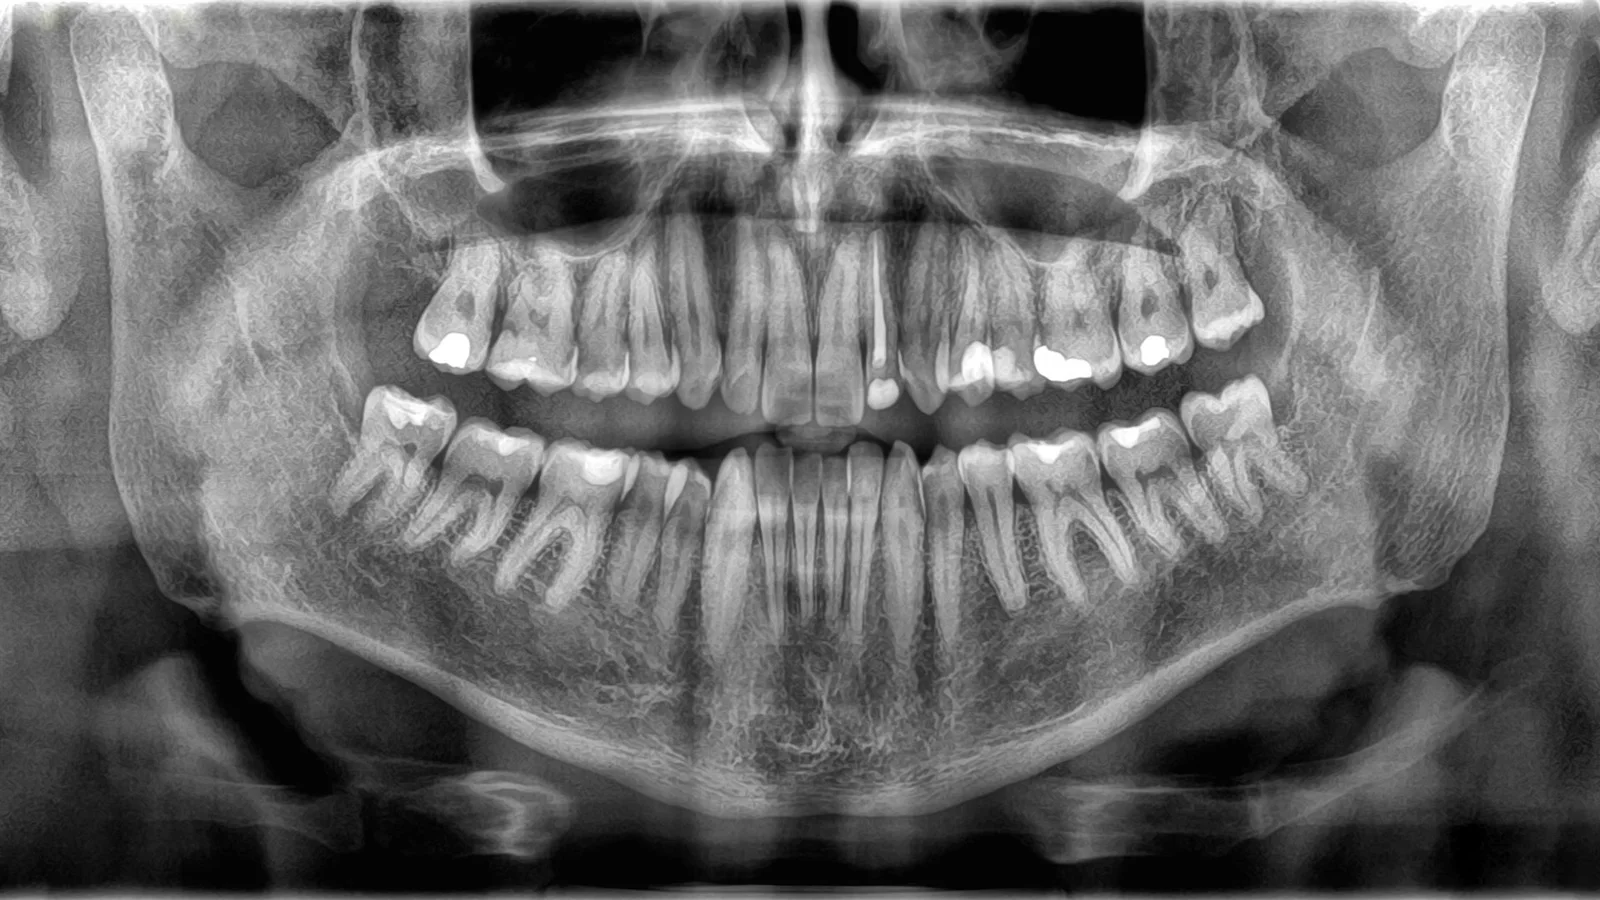

Are Teeth Considered Bones?

Teeth and bones are both hard, mineral-rich tissues, but they differ significantly in function, structure, and living tissue status. Teeth are primarily for digestion and speech, made of enamel, dentin, and pulp, and are non-living tissue once formed. Bones support the body, protect organs, and are living tissues that constantly remodel through blood vessels and cells, which teeth do not have. These differences explain why teeth are not classified as bones.